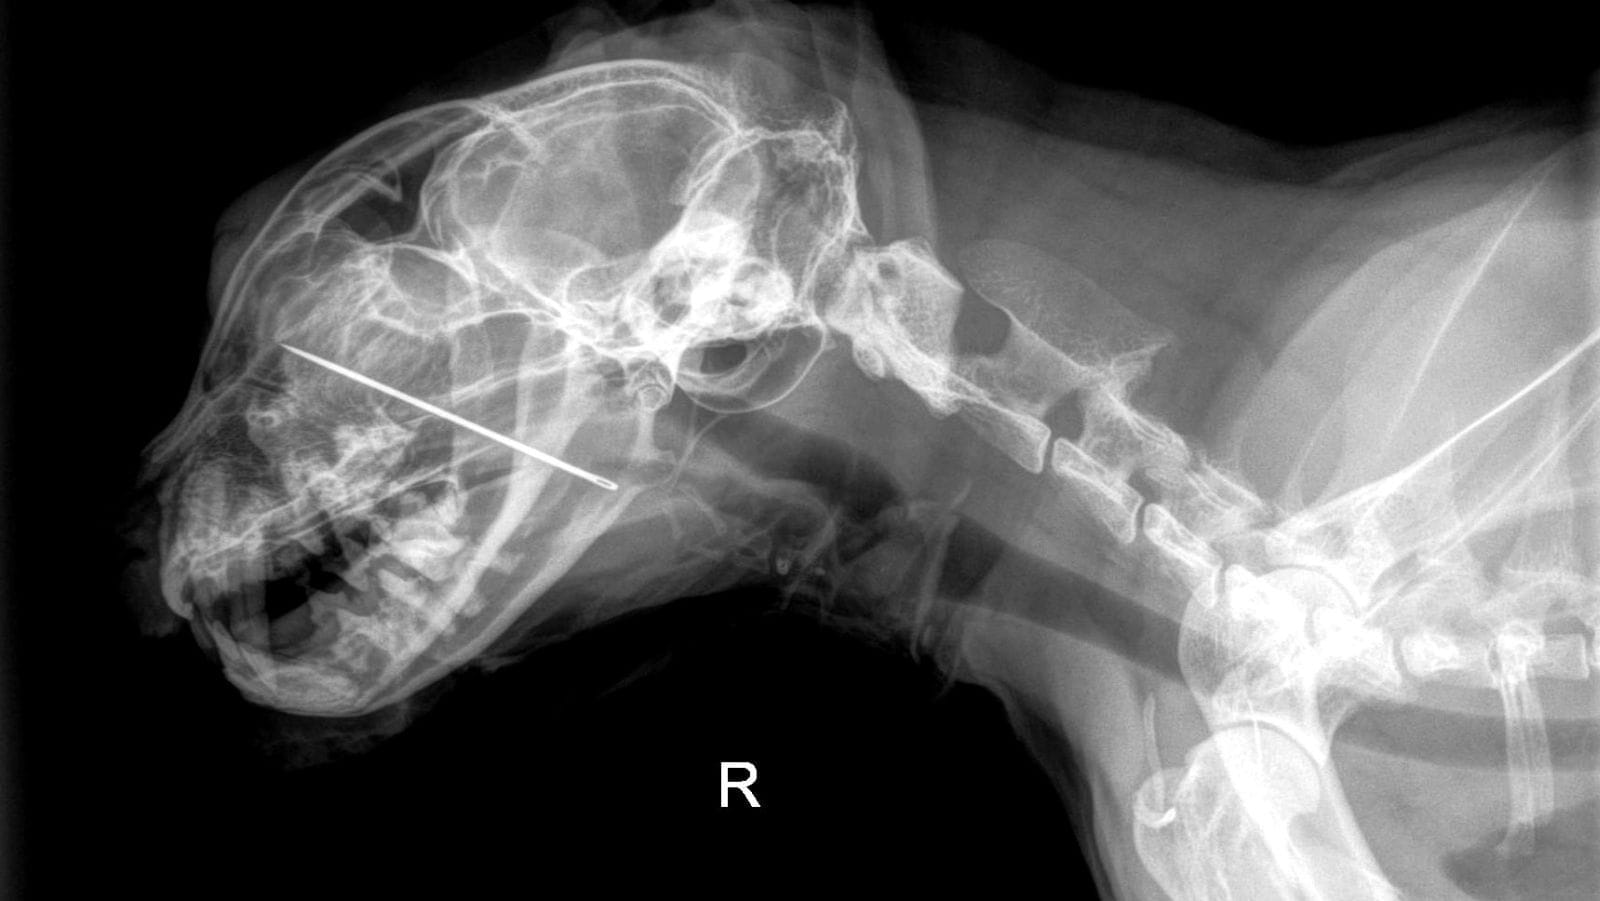

A sewing needle, almost two inches long, was lodged deep in Kevin’s mouth.

It had pierced his hard palate and extended up into his nasal cavity, a spot that’s incredibly difficult to reach and can cause intense discomfort. It was no wonder Kevin was in such distress.

The medical team acted quickly. Using their specialized equipment and surgical skills, they managed to remove the needle completely.